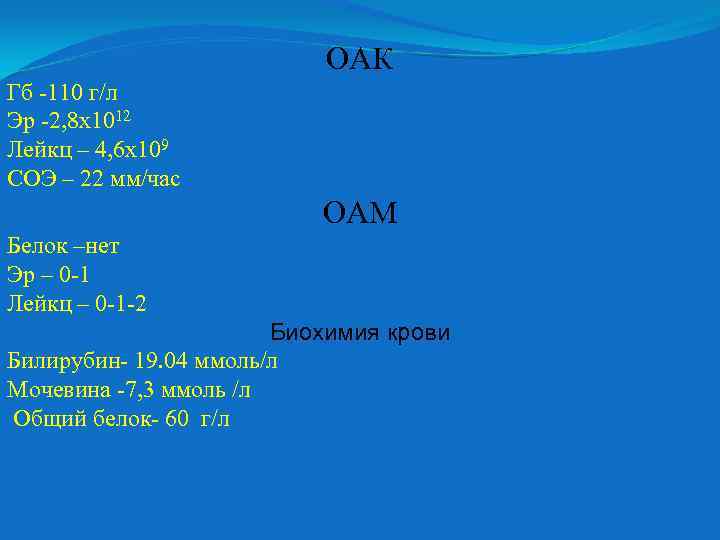

ОАК Гб -110 г/л Эр -2, 8 х1012 Лейкц – 4, 6 х109 СОЭ – 22 мм/час ОАМ Белок –нет Эр – 0 -1 Лейкц – 0 -1 -2 Биохимия крови Билирубин- 19. 04 ммоль/л Мочевина -7, 3 ммоль /л Общий белок- 60 г/л